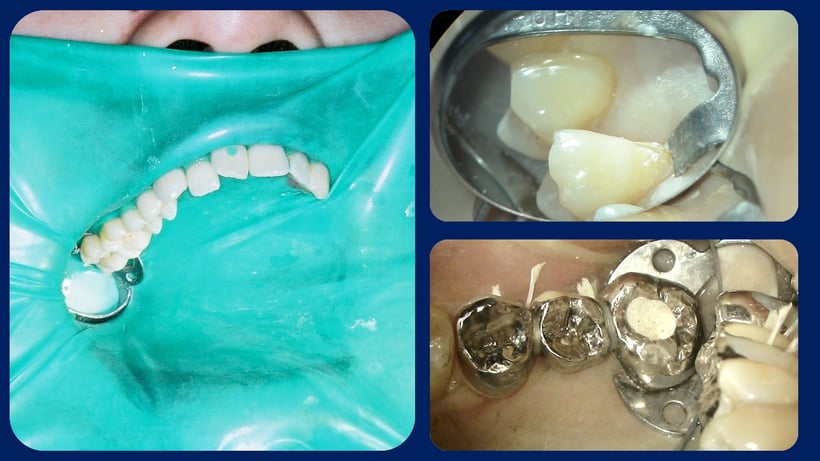

修復治療では10本歯を露出させて治療します。(左)

歯の根元の治療では専用のクランプを使います。(右上)

ブリッジの際はラバーダムを切るか、フロスで結んで防湿します。(右下)

根の治療を行う場合のラバーダムのかけ方。根の治療の時、かぶせ物を完全に取り除いてはいけない。

感染を防ぐため、歯の周りが残るように修復物を残して根に到達するの穴をあけます。

詰め物を外さず、咬合接触部分は削らない

かぶせ物を外して根管治療を行うとラバーダムの防湿性が失われ治療の成功率は下がります。